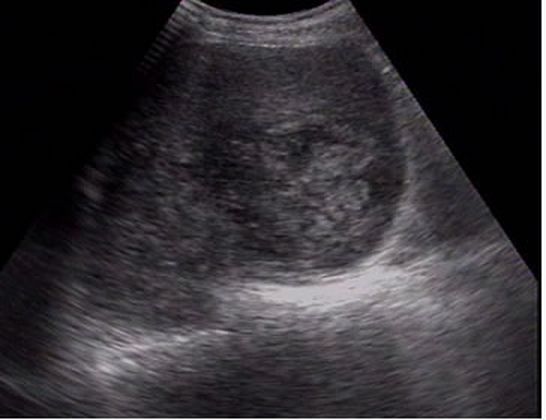

Neoplasias malignas primarias Módulo satélite (flecha). Carcinoma hepatocelular con aguja |